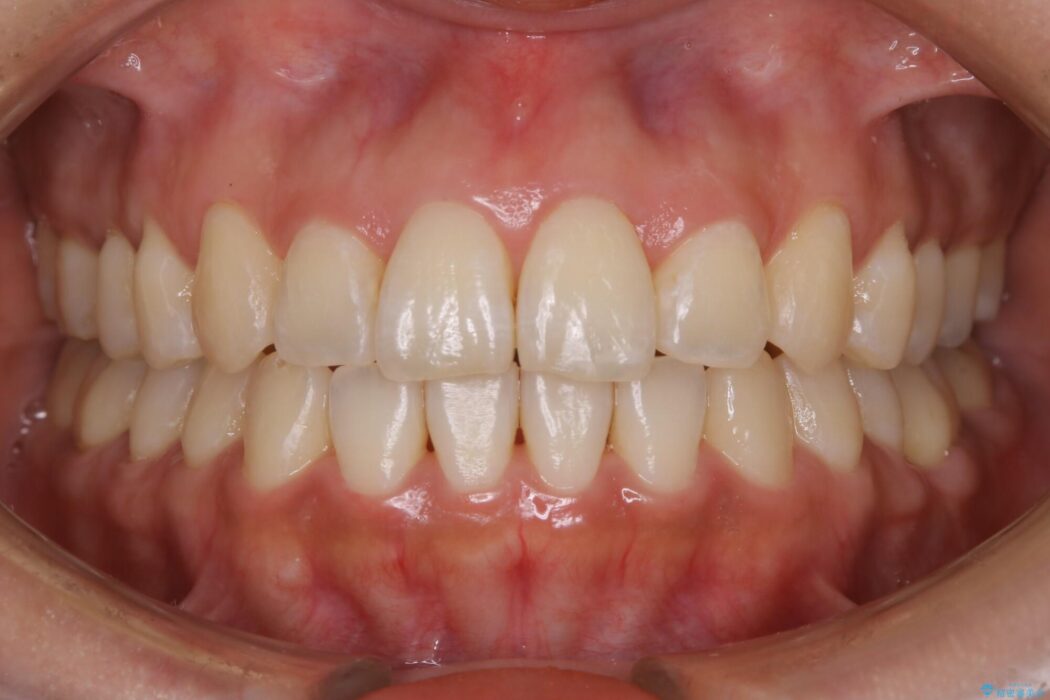

【20代女性】開咬の隙間と歯列の凸凹をまとめて改善する

開咬により上下の噛み合わせが悪く、歯列の凸凹も合わせて治療したいとのことで来院されました。

きちんと装着時間を守っていただいたこともあり、きれいな歯並びを獲得できました。